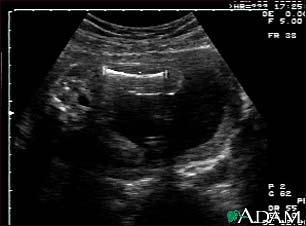

Ultrasound, normal fetus - femur measurement

This is a normal ultrasound of the fetus performed at 19 weeks gestation. A clear view of the left femur (the large bone of the leg) can be seen in the middle, towards the top of the ultrasound screen.